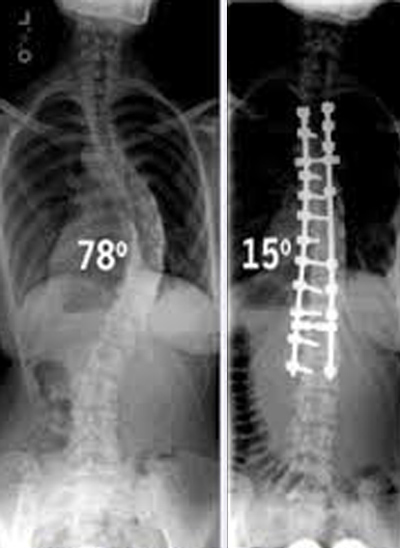

Εξαρτάται από το βαθμό της σκολίωσης που μετριέται με μοίρες επάνω στην ακτινογραφία και από το αν ο ήβος είναι εμφανής ή όχι.

Στις μεγάλες σκολιωτικές γωνίες (πάνω από 45⁰) χρειάζεται εγχείρηση (σπονδυλοδεσία) που σήμερα είναι σχετικά εύκολη και αντιμετωπίζει καίρια το πρόβλημα, ώστε το σώμα ν΄ αποκτά φυσιολογική εμφάνιση.

Ο έλεγχος της εξέλιξης μιας σκολίωσης είναι κλινικός (γιατρός) και ακτινολογικός μέχρι να σταθεροποιηθεί λόγω ηλικίας (16-17 ετών) με 6μηνες επισκέψεις.